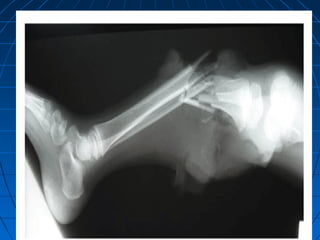

Extremity InjuryExtremity Injury Traumatic amputation, fractures, crush injuries,Traumatic amputation, fractures, crush injuries,

Blast Extremity InjuriesBlast Extremity Injuries

Traumatic amputationTraumatic amputation

Blast Extremity InjuriesBlastExtremity Injuries Traumatic amputationTraumatic amputation Initial ManagementInitial Management ••Even when blast victims have small entrance wounds,Even when blast victims have small entrance wounds, surgeons should maintain a low threshold for performingsurgeons should maintain a low threshold for performing thorough debridementthorough debridement ••All open fractures are considered contaminated andAll open fractures are considered contaminated and should receive early antibiotic treatment (first generationshould receive early antibiotic treatment (first generation cephalosporin and/or aminoglycoside, extended spectrumcephalosporin and/or aminoglycoside, extended spectrum penicillinpenicillin(( ••Obviously contaminated wounds should be irrigated withObviously contaminated wounds should be irrigated with sterile saline and dressed with iodophore (Betadine)-sterile saline and dressed with iodophore (Betadine)- soaked sponges; once dressed, re-exposure should waitsoaked sponges; once dressed, re-exposure should wait until operative explorationuntil operative exploration